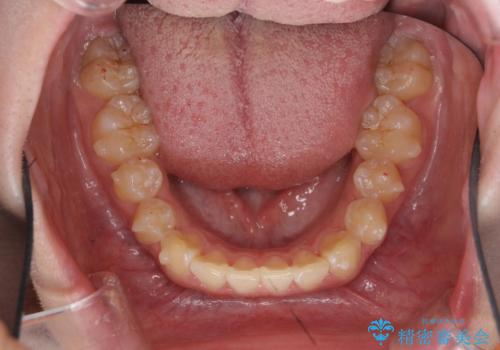

前歯のがたつき気になる。インビザラインモデレート

- 前歯のがたつきが気になるとの事で来院。

マウスピース矯正希望でしたのでインビザラインモデレートで治療を行いました。

がたつきが無くなり満足して頂けました。

矯正が終わった後は保定装置を使用しないと後戻りしてしまうのでしっかりと保定装置を使用する必要があります。